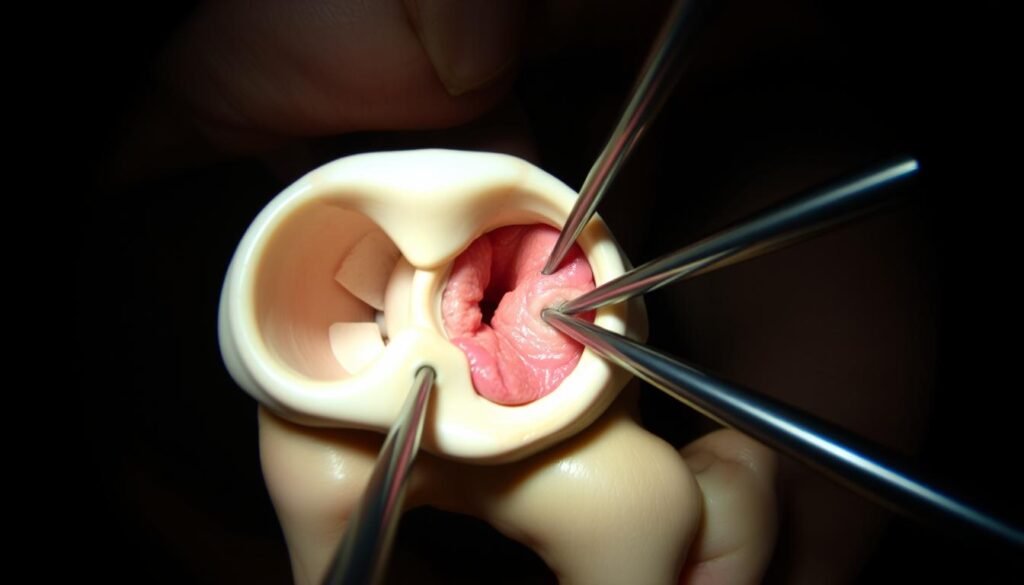

Arthroskopische Verfahren

Die Kniegelenkspiegelung (Arthroskopie) wird häufig ergänzend eingesetzt:

- Entfernung oder Refixierung abgesprengter Knorpel-Knochen-Fragmente

- Behandlung von Knorpelschäden an der Rückseite der Kniescheibe

- Diagnostische Beurteilung des Gelenkinneren

Arthroskopische Ansicht des Kniegelenks: Beurteilung von Knorpelschäden nach Patellaluxation